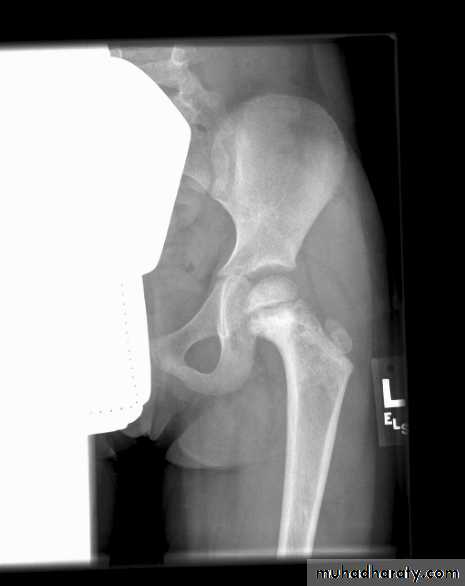

Bone tumors

Bone Tumors in ChildhoodAge – Adolescents > younger children

Ewing Sarcoma

All bones:

Long: diaphyses

Flat

Pelvis

Skull

Ribs

Presentation of Bone Tumors

Plain X-Rays are usually abnormalClassic X-ray of Ewing:

Moth-eaten

lytic lesion

Classic X-ray of Ewing: